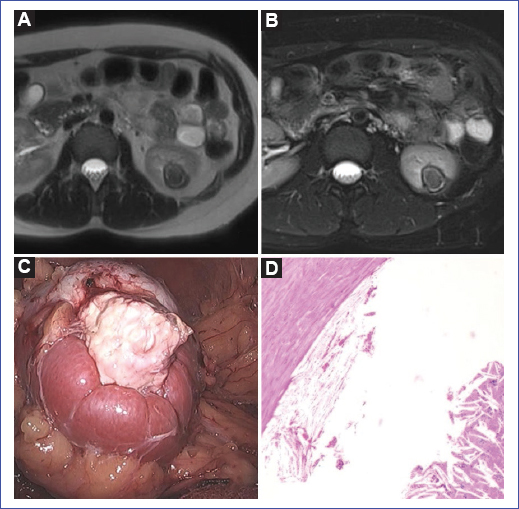

Mujer de 26 años, asintomática, que acude referida por el hallazgo incidental de una masa renal evidenciada por ecografía. En los exámenes complementarios de orina se evidencia microhematuria, y los de imágenes muestran una tumoración de 2,2 × 2,8 cm sugestiva de proceso neoformativo (Figs. 1 A y B). Se conversa con la paciente sobre las opciones terapéuticas y se opta por la cirugía. Se realiza nefrectomía parcial laparoscópica sin complicaciones (Fig. 1C) y la paciente evoluciona favorablemente (Tabla 1). En la anatomía patológica se concluye como granuloma de colesterol renal sin signos de malignidad (Fig. 1D). Se realizan exámenes complementarios, que revelan niveles de colesterol elevados. En la actualidad, la paciente tiene una evolución favorable en tratamiento de hipercolesterolemia (Fig. 1).

Figura 1. A: secuencia T2, imagen periférica hipointensa con componente medial hipointenso. B: secuencia T1 poscontraste sin realce significativo. C: imagen laparoscópica de la masa renal en el polo inferior derecho, exofítica, de color blanco y consistencia dura a la manipulación. D: fotomicrografía con tinción de hematoxilina y eosina que muestra pseudocápsula fibrosa y en la luz presencia de granuloma de colesterol asociado a extensa necrosis y detritus celular.